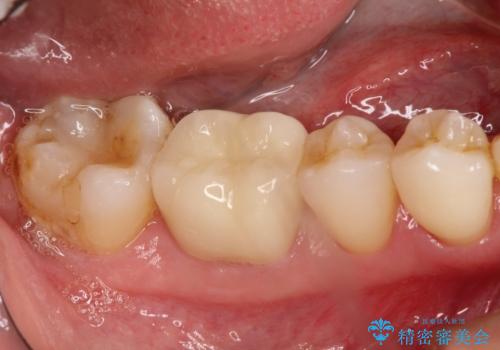

40代男性 保険治療の現実

- 40代男性

- 保険治療による金属の詰め物を除去

→古い材料、虫歯を徹底的に除去

→欠損を新しく修復

→被せもの、詰め物の再作

保険治療の金属充填物を外し、メタルフリーのセラミックにて再修復します。

実際には、保険治療の下には粗悪なセメントが劣化し、2次的な虫歯が広がっている事が多く、これらの処理に多大な労力を費やすこととなります。

患者さんには見えない部分であり、レントゲンでもわからないため、往々にして手を抜かれる部分です。

自費診療でさえこういった部分に妥協する治療は数多く見受けられます。

被せものの種類:ジルコニアオールセラミック スタンダード

e.max プレスインレー

今回は処置範囲に被り親知らずが歯ぐきの中に埋まっていたため抜歯しました。

抜歯に伴いやや深い歯周ポケットを許容した状態で最終的な被せものを製作することとなったため、ここは今後のメインテナンスを通してフォローしなくてはなりません。